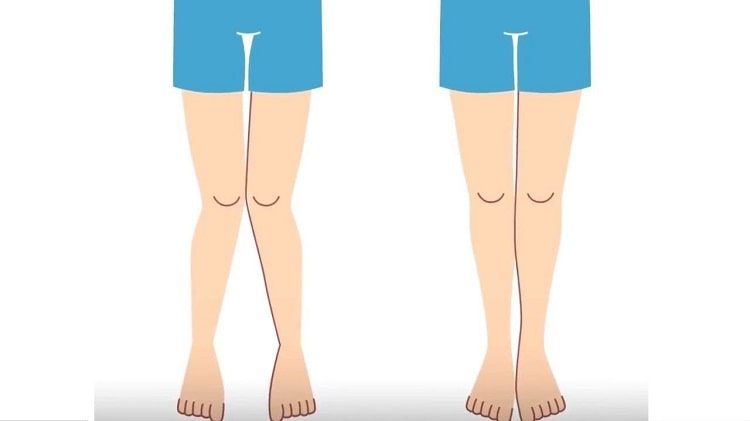

- داشتن کف پای صاف